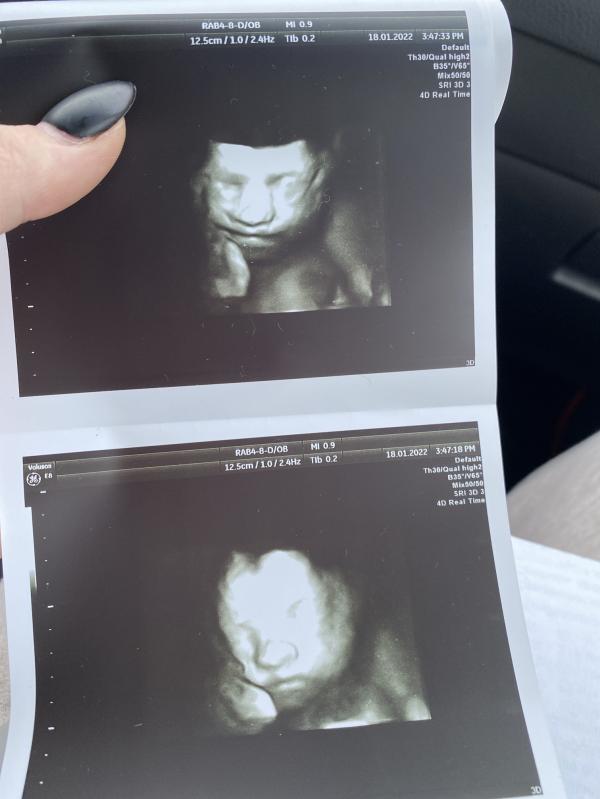

Дочь ещё не родилась, а уже имеет вредный характер овна😹 ходили сегодня на 3д узи и вот эта мадам закрыла своё личико ногами и рукой, отправили поболтаться по коридору, не помогло🥲 в итоге выпила сладкий кофе и съела маленькую шоколадку, буквально на минуты 3 мадмазель соизволила нам показаться и с первой секунды показала язык 😹🙈 потом приняла тоже положение) все же мы успели сделать годные снимочки) были в арнике у романовской 🥰

27 недель